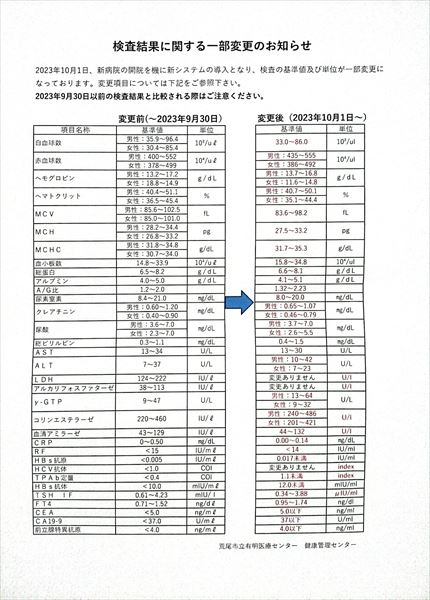

0140 健康診断結果

0109 24.7.29健康診断=pdf

0108 ①22.8.23荒尾市民病院=pdf ②2023-08-21健康診断結果.pdf 8/10(木)受診 荒尾市民病院